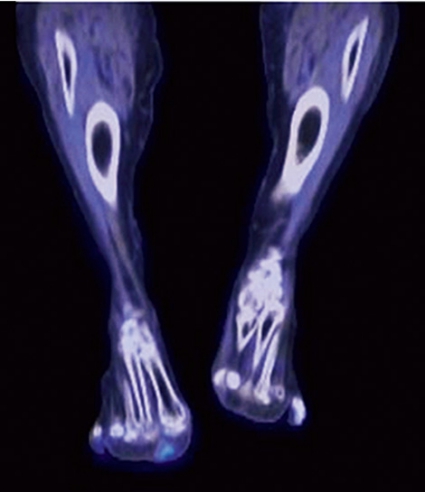

Patienten som beskrevs inledningsvis hade förhöjt FGF23, 90 ng/l (referensvärde 10–50 ng/l), och hon genomgick en venkatetrisering där en klar gradient påvisades från höger ben. Därefter undersöktes benet med MR och oktreotidskintigrafi utan något klart fynd. Upprepad katetrisering kunde påvisa en gradient så distalt man kom i höger nedre extremitet, och FDG-PET kunde därefter påvisa ett fokalt upptag i framfoten (Figur 2). En liten tumör av typen PMT-MCT avlägsnades, fosfatmetabolismen normaliserades, och patientens kliniska tillstånd förbättrades dramatiskt under de närmaste månaderna.